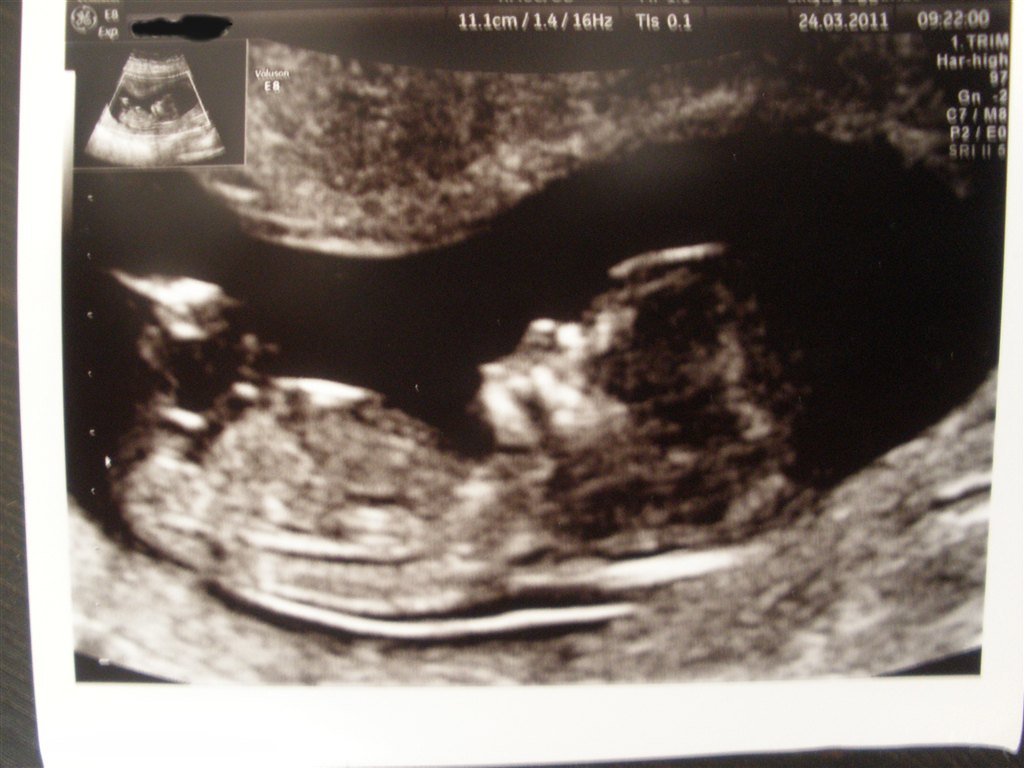

Glæd dig! Det er bare det største nogensinde!! Jeg var vist nok 12+4, og fik disse skønne billeder af prinsessen. Synes især det ene er FANTASTISK, det med hovedet bare. Fordi man kan se hendes hånd med alle 5 fingre knyttet sammen

Vedhæftede fotos (klik for at se i fuld størrelse)